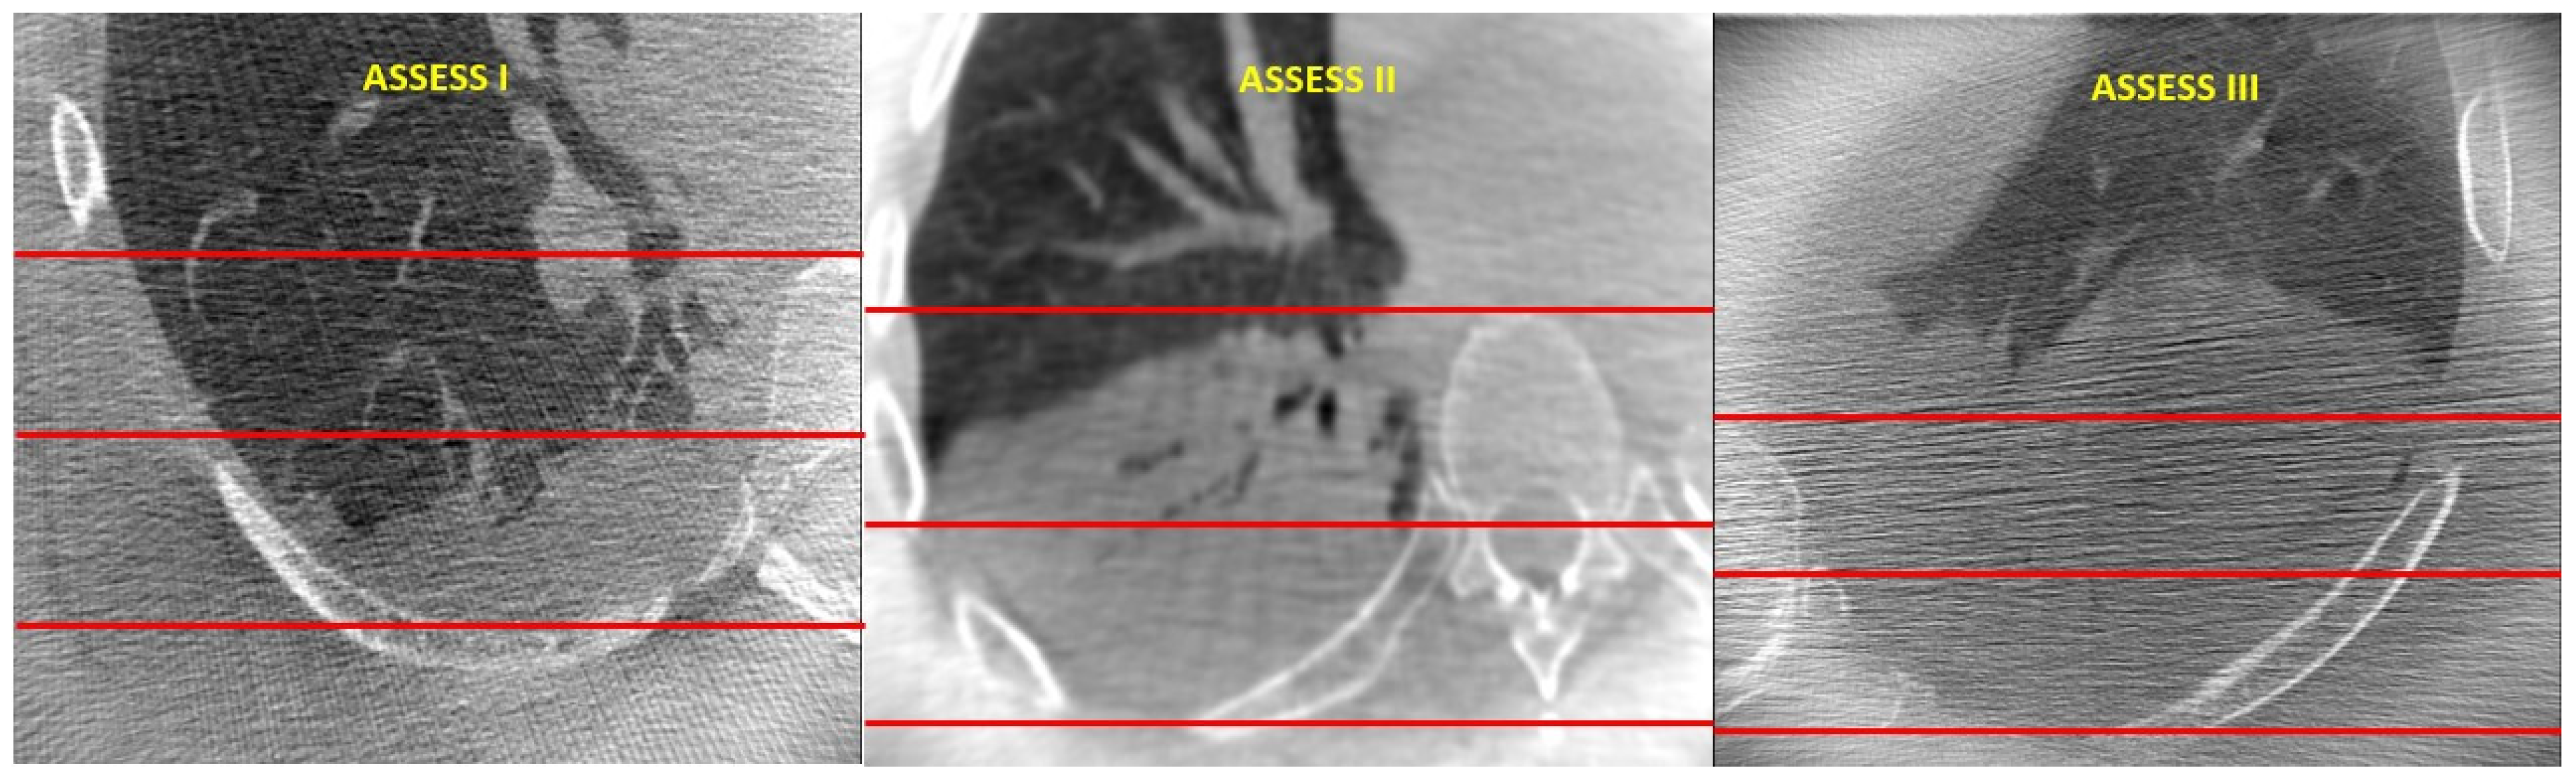

Severity of Atelectasis during Bronchoscopy: Descriptions of a New Grading System (Atelectasis Severity Scoring System—“ASSESS”) and At-Risk-Lung Zones

Khan, A.; Bashour, S.; Sabath, B.; Lin, J.; Sarkiss, M.; Song, J.; Sagar, A.-E.S.; Shah, A.; Casal, R.F. Severity of Atelectasis during Bronchoscopy: Descriptions of a New Grading System (Atelectasis Severity Scoring System—“ASSESS”) and At-Risk-Lung Zones. Diagnostics 2024, 14, 197. https://doi.org/10.3390/diagnostics14020197